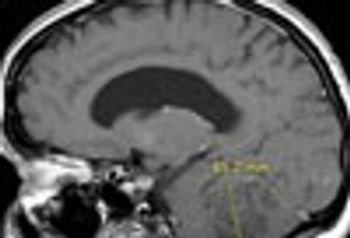

Spinal problems include epidural abscess, paravertebral muscle atrophy, Chiari I malformation, osteomyelitis/discitis, diastematomyelia, spinal compression, spinal tuberculosis.